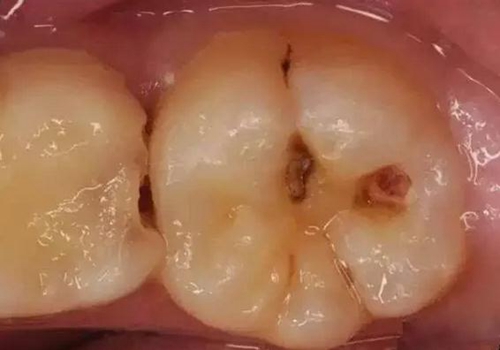

第二步:中齲

當您吃糖時,感覺酸疼,您說:“沒關(guān)系,不是很疼。”

牙醫(yī)卻說:“這時病變已經(jīng)破壞到牙本質(zhì)淺層了,牙齒已經(jīng)有齲洞形成,對酸甜食物敏感,需要做充填治療。”